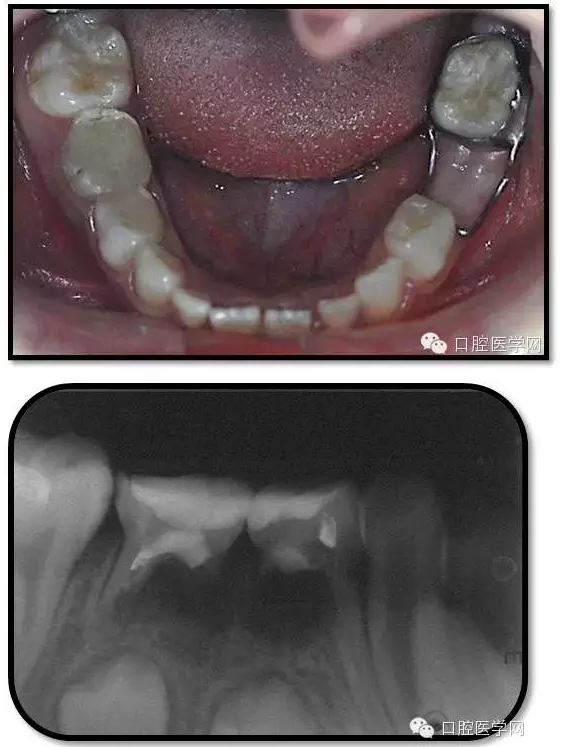

1、根分歧處病變姑息保留牙的治療及轉(zhuǎn)歸。 75牙體缺損過大,根分岐大面積透射影并累及根尖周。故拔除后間隙保持。84、85初診時已做過根管治療,有繼發(fā)齲,牙根吸收較多,可見大面積的根分歧病變,但根尖無病變,考慮44、45表面骨硬板連續(xù),故只對患牙進行了繼發(fā)齲充填治療,姑息保留。3個月復查時,85O、84DO充填完好,邊緣密合,叩(-),不松,齦無紅腫。7個月復查時85O、84DO充填完好,邊緣密合,叩(-),不松,齦無紅腫。X線:84、85根分歧透射影,44、45骨硬板連續(xù)。 回顧整個治療過程,應定期復查84、85姑息保留牙,且間隔時間不宜過長。觀察根分歧病變的恢復情況,一旦發(fā)現(xiàn)恒牙胚受累及,則需采取積極措施。

2、75OL、85O、84DO發(fā)生根尖及根分歧病變原因 追溯75OL、85O、84DO就診之前病史,84是因慢性根尖周炎1年前行根管治療,治療當時根充滿。75、85因慢性牙髓炎1年前行根管治療,治療當時根充滿。這幾個牙當時牙體缺損均較大,未行預成冠修復,隨后充填體脫落,發(fā)生繼發(fā)齲,患兒1年一直未定期復診,導致口腔內(nèi)感染通過冠方造成根分歧和根尖的炎癥。所以總結(jié)以上,對于大面積齲壞牙根管治療后應定期復查,并行預成冠修復。